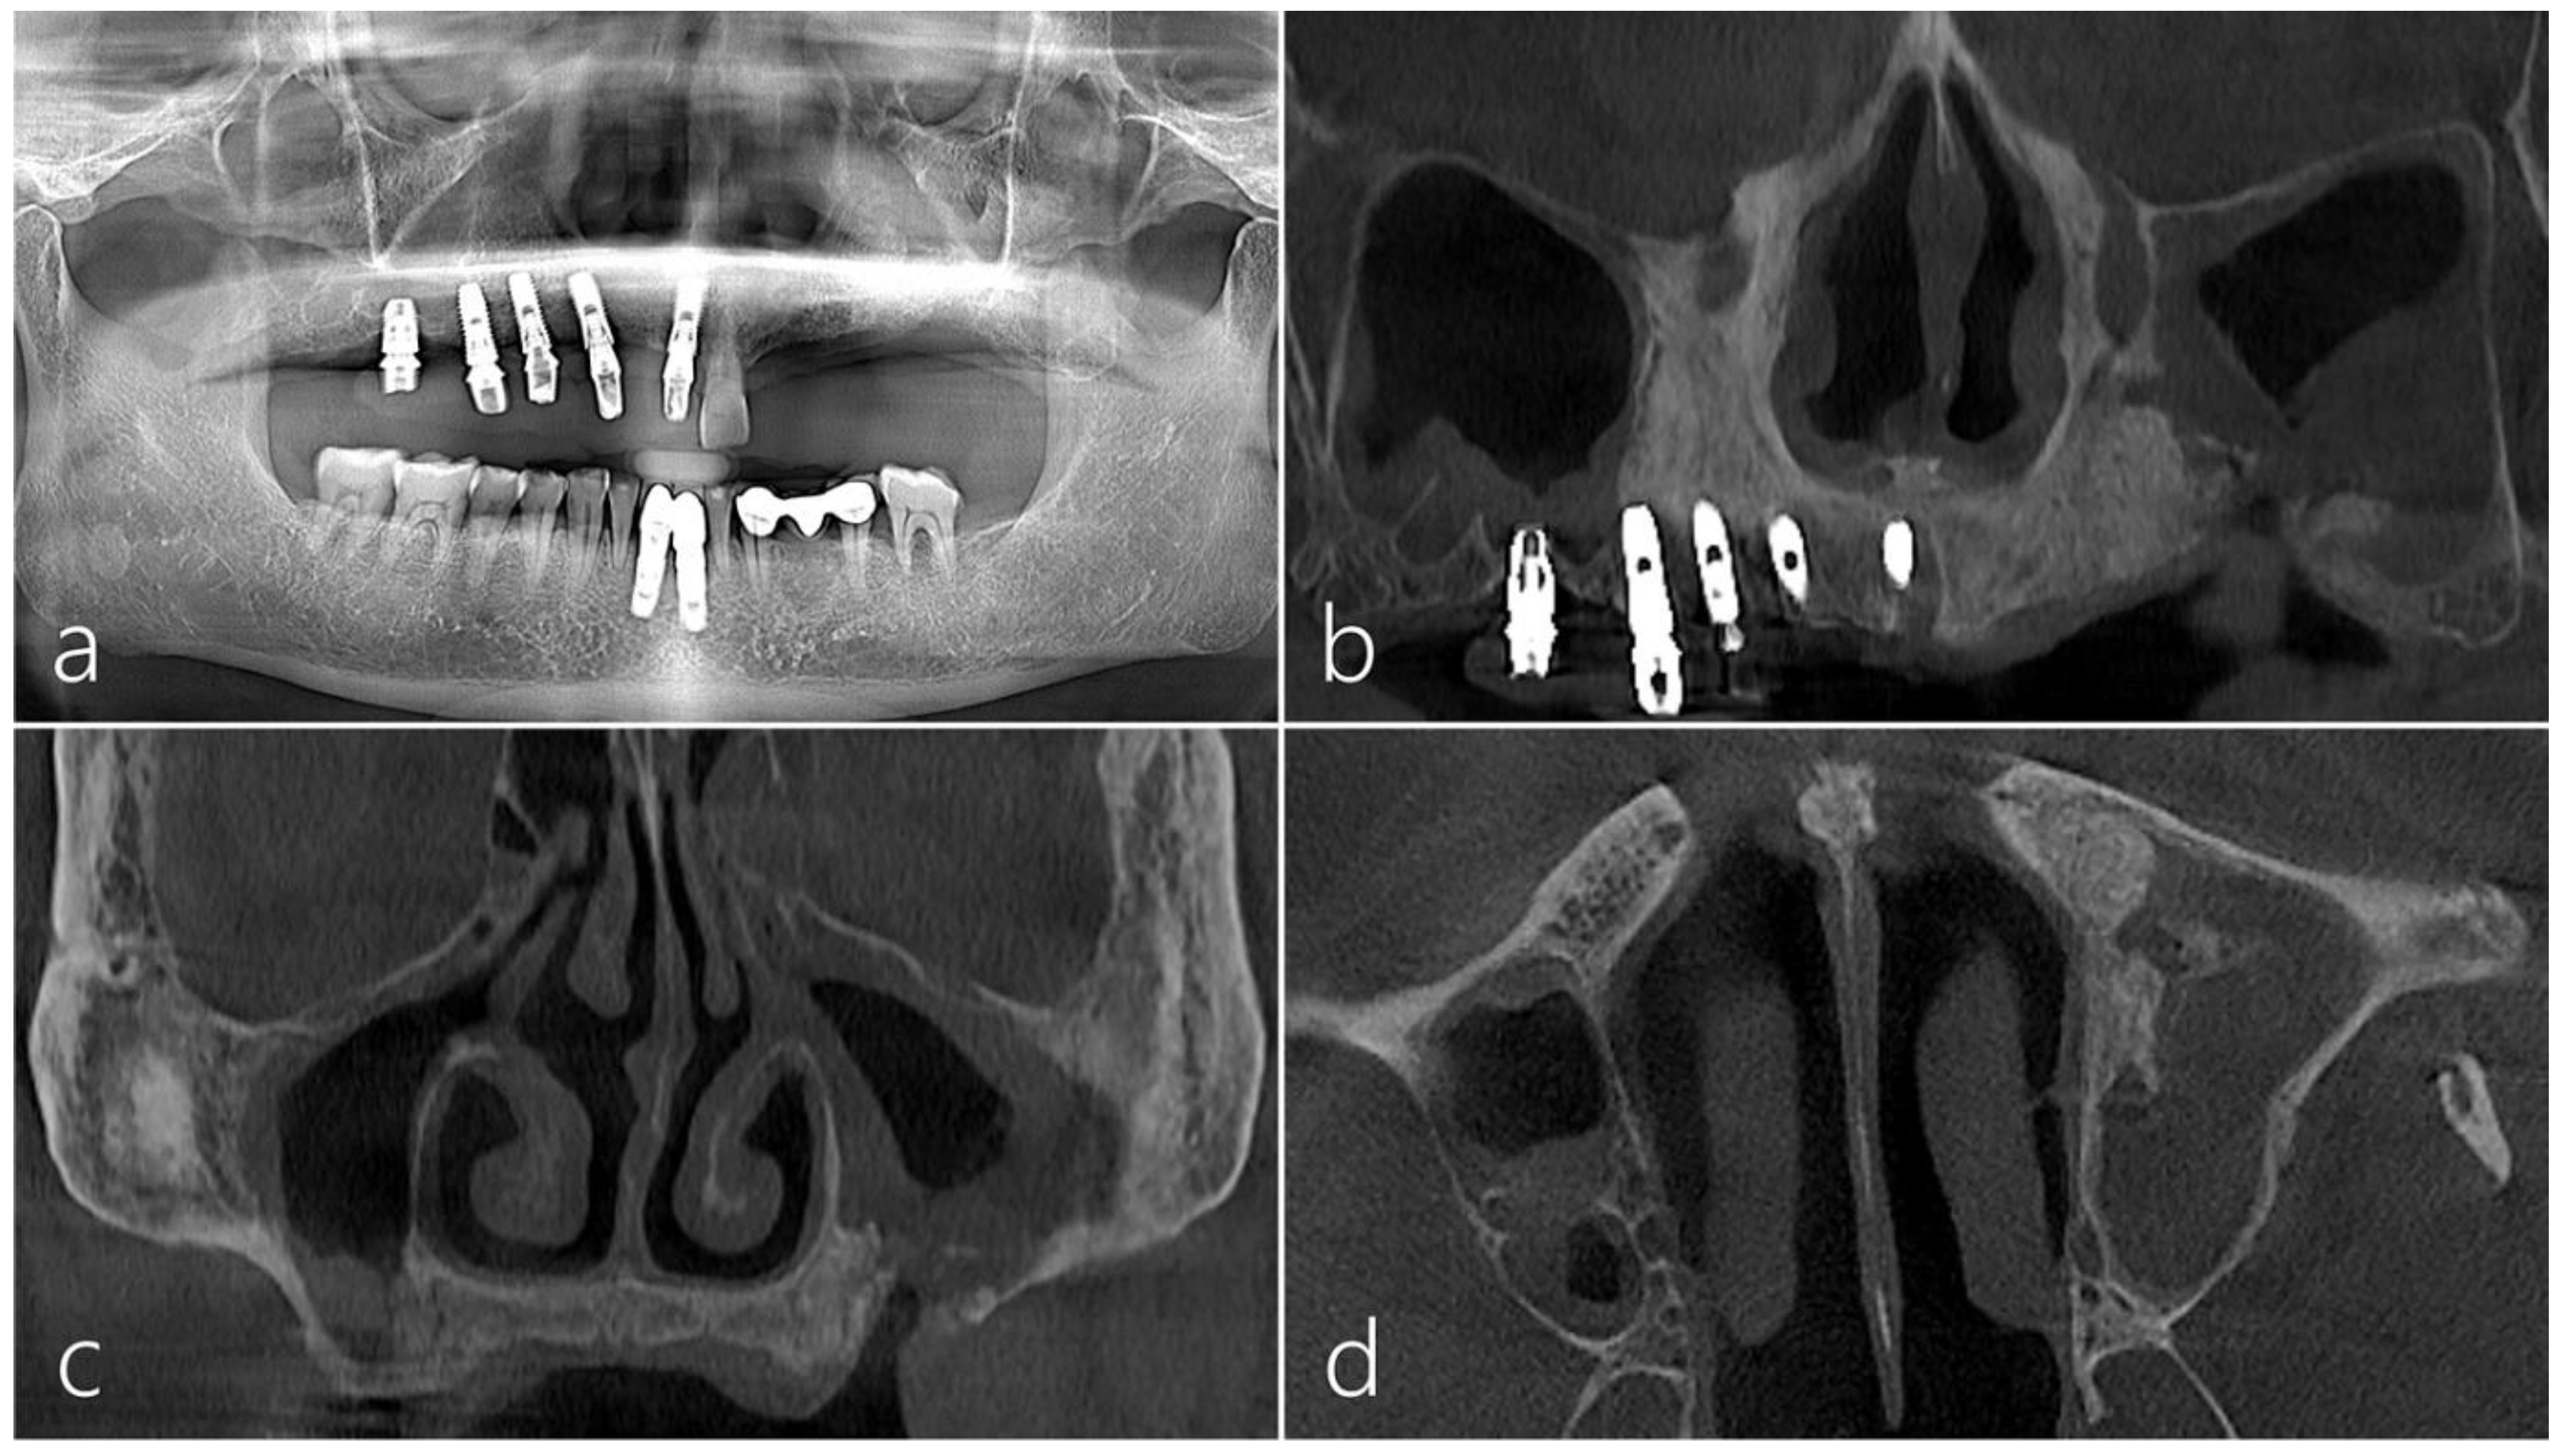

2.1. Case 1